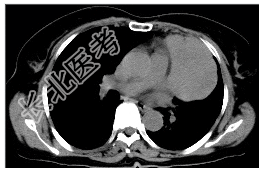

- [材料题] 病历摘要:女,56岁。因胸部不适,2月来诊,无发热,无咯血。起病以来体重明显减轻。查体:左胸呼吸音减弱,左上胸扣诊浊音。胸部X线片示“左上肺占位病变”。做胸部CT线检查。

- 简答题1、诊断及依据是什么?

- 简答题2、鉴别诊断有哪些?